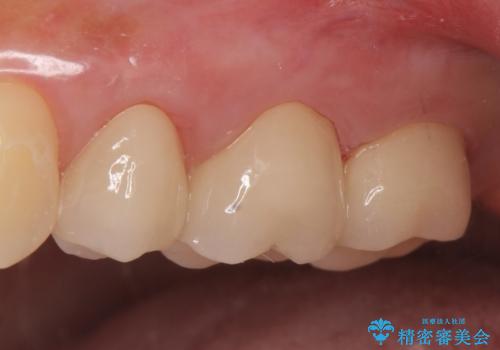

左上5は再根管治療を行い症状の緩解を確認後、オールセラミッククラウンによる補綴を行いました。

左上6、7番目の歯もしみるとのことだったので古い樹脂及び虫歯を除去後、オールセラミッククラウンによる補綴を行いました。

今回用いたオールセラミッククラウンはジルコニアフレームという白い素材の上にセラミックを盛っているため、審美性が非常に高いのが特徴です。

また、ジルコニアは人工ダイヤモンドの材料にも使われているほど高い強度を持っており、そのためオールセラミッククラウンは審美性だけでなく、奥歯やブリッジの補綴も可能とするクラウンです。